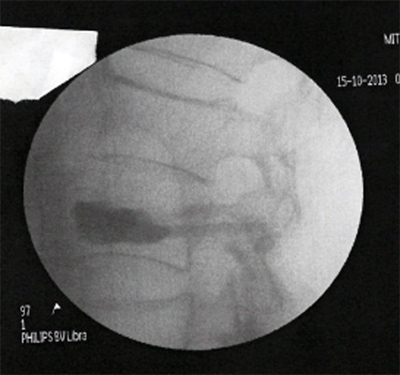

Η λύση αυτή ονομάζεται κυφοπλαστική. Χωρίς ανοικτή εγχείρηση, μέσω μίας χοντρής βελόνας (trocard) και παρακολουθώντας τη διαδρομή μέσω ακτινολογικής τηλεόρασης, εισάγεται μέσα στο σώμα του σπασμένου σπονδύλου ένα μπαλονάκι που φουσκώνει με νερό. Αναλόγως της πίεσης που ασκείται, ο σπόνδυλος διορθώνεται.

Στην κοιλότητα που δημιουργείται εισάγεται ακρυλικό τσιμέντο που όταν πήξει μετά μερικά λεπτά, καθιστά σταθερό και πάλι τον σπόνδυλο.

Η διαδικασία γίνεται με γενική νάρκωση και διαρκεί ¾ της ώρας. Μετά λίγες ώρες παραμονής στο νοσοκομείο, ο ασθενής επιστρέφει σπίτι του και από την επομένη κυκλοφορεί χωρίς πόνο, χωρίς κορσέ και χωρίς να γέρνει.